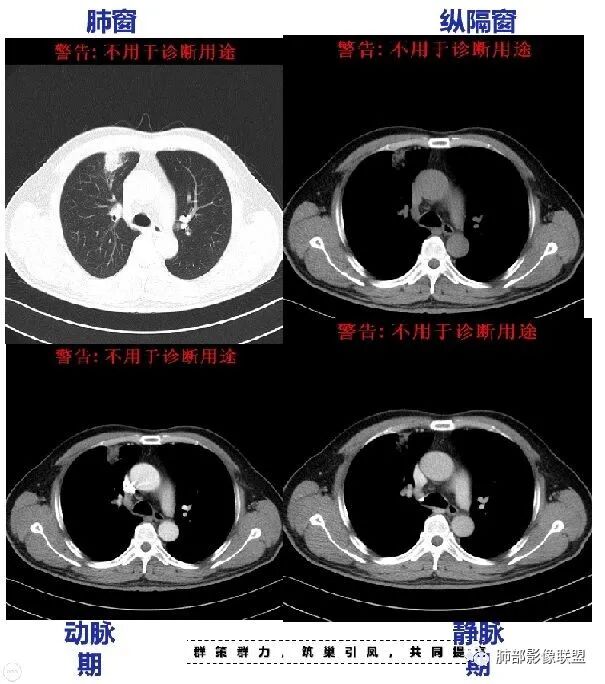

回顾性分析本病例,小编觉得鉴别诊断聚焦于肺鳞癌和炎性病灶(包括结核)之间,这个病灶的炎性征象大于恶性征象;以下是这个病例的的炎性征象:①病灶边缘平直收缩为主,也缺少典型的分叶毛刺;②支气管走行于病灶中央截断,断端比较圆钝;③近端引流支气管壁增厚;④整体强化不显著,坏死区太圆太规整,边缘隐约显示强化的环;⑤血管走形自然,未见明显破坏征象;⑥胸膜外脂肪间隙增宽,胸膜广基地增厚,未见栽赃;⑥52岁偏年轻(此条也不大支持鳞癌)

虽然本例患者支气管截断,病灶中央截断炎性及恶性都可以,断端向病灶一侧圆钝更支持炎性。

南边:实质部分强化均匀。总体倾向于炎性病变,部分区域膨隆,肿瘤性病变待排。

南边:低密度灶确实没看到明显的强化环内壁。

这个层面环形强化挺明显。